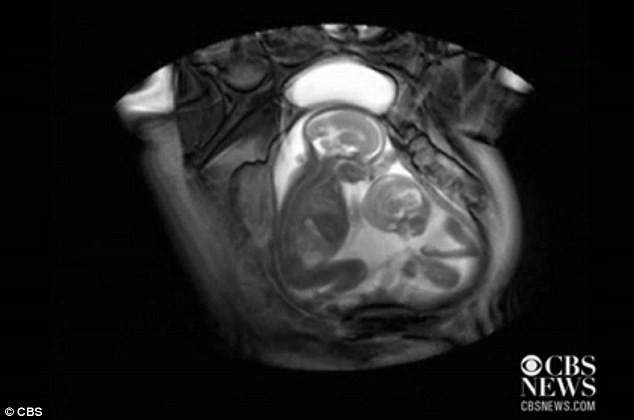

| Em bé nhỏ hơn đang đạp em bé lớn hơn để tranh chỗ để chân. |

Những hình ảnh tuyệt vời này được ghi lại bởi trung tâm chăm sóc thai nhi Imperial College London bằng thiết bị MRI.

Ban đầu, Imperial College London sử dụng thiết bị MRI để chẩn đoán một hội chứng có khả năng gây tử vong được gọi là hội chứng truyền máu song thai. Hội chứng này chỉ xảy ra ở các cặp song sinh giống hệt nhau khi máu từ một thai nhi này truyền sang cho thai nhi kia.